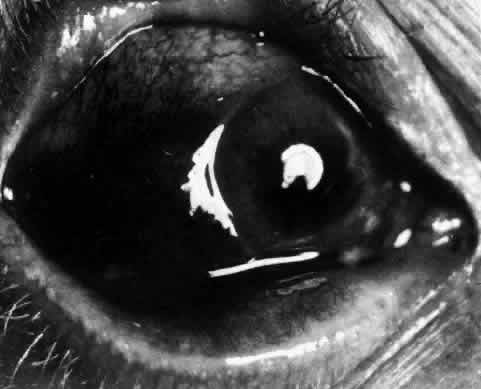

Simple and nodular episcleritis differ in their clinical courses, but in both the edema and infiltration are entirely within the episcleral tissues. The sclera is not involved. The maximum congestion is in the superficial episcleral network, with some slight congestion of the conjunctival vessels and deep episcleral vessels (Fig. 10). The intraocular structures are not involved in either variety, nor is the visual acuity affected. Anterior segment fluorescein angiography reveals a normal vascular pattern but a very rapid flow rate, with the whole transit of the dye being completed within 2 or 3 seconds (Figs. 11 and 12).

Fig. 10. Maximum congestion in the superficial vascular plexus in episcleritis. The conjunctival and deep episcleral networks are separated from the deep plexus by edema and infiltration in the episcleral tissue. (Watson PG, Hayreh S, Awdry P: Episcleritis and scleritis. Br J Ophthalmol 52(3):278–279, 1968)

The redness of simple episcleritis may be intense, varying from a fiery-red or a brick-red discoloration to a mild red flush, but it does not have the bluish tinge that is seen in scleritis. The distribution is usually sectorial but can involve the whole anterior segment of the globe. The episcleral vessels are engorged but retain their normal radial position and architecture (Figs. 13 and 14; Color Plate 1A). In simple episcleritis, there is a diffuse edema of the episcleral tissues. These tissues are sometimes infiltrated with gray deposits that appear yellow in red-free light. Surprisingly, the eye is rarely tender to the touch.